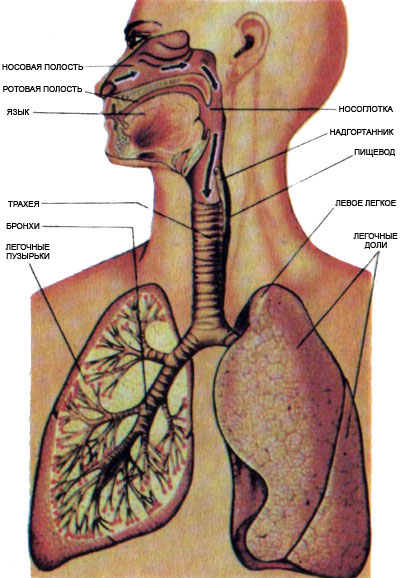

Схема дыхательной системы человека: а — общий план строения; б — строение альвеол; 1 — носовая полость; 2 — надгортанник; 3 — глотка; 4 — гортань; 5 — трахея; б — …

Дыхательные пути представляют собой систему трубок, просвет которых формируется благодаря наличию в них костей и хрящей . Внутренняя поверхность дыхательных путей …

Дыхательнаясистемачеловекасостоитизтканейиорганов,обеспечивающихлегочную вентиляциюилегочноедыхание .К воздухоносным путям относятся: нос, полость носа, носоглотка, …

Дыхательная система выполняет жизненно важную функцию — обеспечение клеток организма кислородом и освобождение их от углекислого газа, являющегося конечным продуктом …

Дыхательная система (дыхательный аппарат), systema resperatorium, состоит из дыхательных путей и парных дыхательных органов - легких . Дыхательные пути …

Дыхательная система . Дыхание как совокупность процессов, обеспечивающих поступление в организм кислорода и удаление углекислого газа . Органы, входящие в состав верхних …

Основной механизм регулирования дыхания — центральная нервная система . Дыхательный центр регулирует частоту и ритм дыхания .